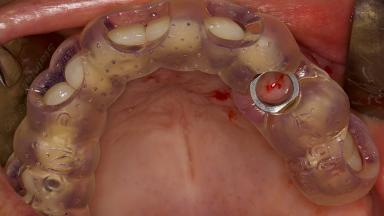

In this short microlearning module on digitally guided sinus floor elevation, we delve into a specialized aspect of the digital workflow for implant-guided surgery, focusing on the use of digital guides in the sinus floor elevation technique.

• define the manufacturing process of digital guides for SFE

• explore the intraoperative use of digital guides in SFE